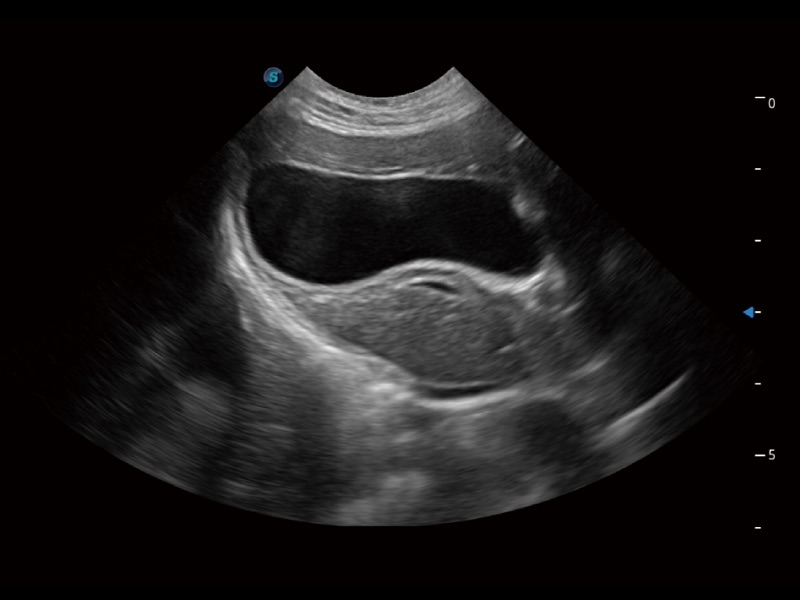

大型犬、馬科、農(nóng)場動物及大型異寵動物

通過創(chuàng)新的 Matrix E自適應(yīng)濾波器和超長時間域算法,極大提升超低速微細血流的檢出能力,同時更精準地濾除軟組織和噪聲信號,為獸用醫(yī)生提供以往無法通過常規(guī)血流獲得的疾病診斷信息。

ProPet 70專為動物醫(yī)生設(shè)計,對不同的動物體型和生理結(jié)構(gòu)作出了針對性的優(yōu)化。通過動物影像專用軟件,可滿足個性化的應(yīng)用需求,幫助動物醫(yī)生獲得更精確的診斷數(shù)據(jù)。

ProPet 70 全新的動物超聲智能軟件和豐富的探頭群,為動物醫(yī)生提供了高清晰度和精細分辨率的圖像,無論在寵物、馬科、畜牧還是實驗室動物等應(yīng)用中都可以輕松應(yīng)對,為您的日常工作帶來滿意的體驗。